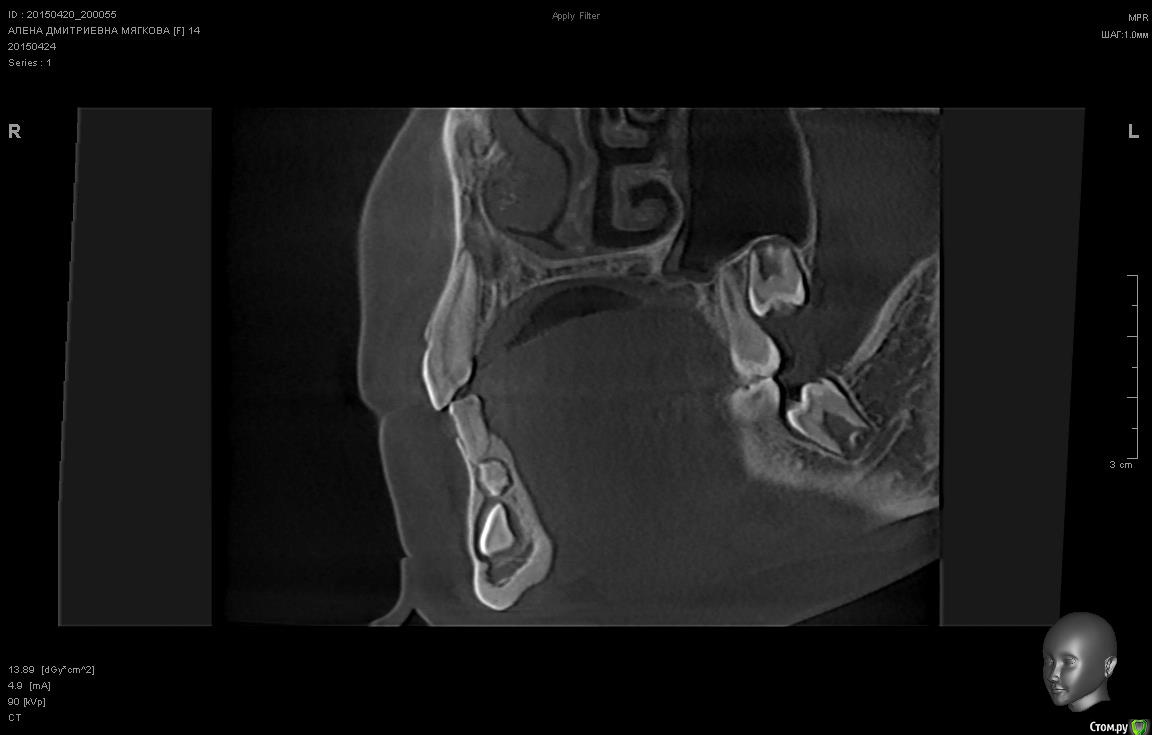

sgeorge Опубликовано 24 апреля, 2015 Автор Поделиться Опубликовано 24 апреля, 2015 КТ сделали, срезы выложу Ссылка на комментарий

voff Опубликовано 24 апреля, 2015 Поделиться Опубликовано 24 апреля, 2015 по кт смотреть где ближе к кортикалке, там и подбираться Ссылка на комментарий

sgeorge Опубликовано 24 апреля, 2015 Автор Поделиться Опубликовано 24 апреля, 2015 Вот некоторые срезы. Вопрос в том, стоит ли браться за ортодонтию. Ортодонта сегодня нет, спросить не могу. Ссылка на комментарий

sgeorge Опубликовано 24 апреля, 2015 Автор Поделиться Опубликовано 24 апреля, 2015 Как-то криво прикрепились, сорри.Думаю, что с таким крючком на апексе ортодонтия отпадет? Тогда стоит ли удалять в настоящий момент или дождаться завершения роста челюсти? Ссылка на комментарий

krokomot Опубликовано 24 апреля, 2015 Поделиться Опубликовано 24 апреля, 2015 Клык то молочный во рту, без ортодонтии все равно не обойтись так что можно попробовать зуб вертикально почти стоит, только кортикалку желательно бы удалить по ходу выдвижения (постепенно). На стрелке думаю одонтома при раскрытии убрать. Ссылка на комментарий